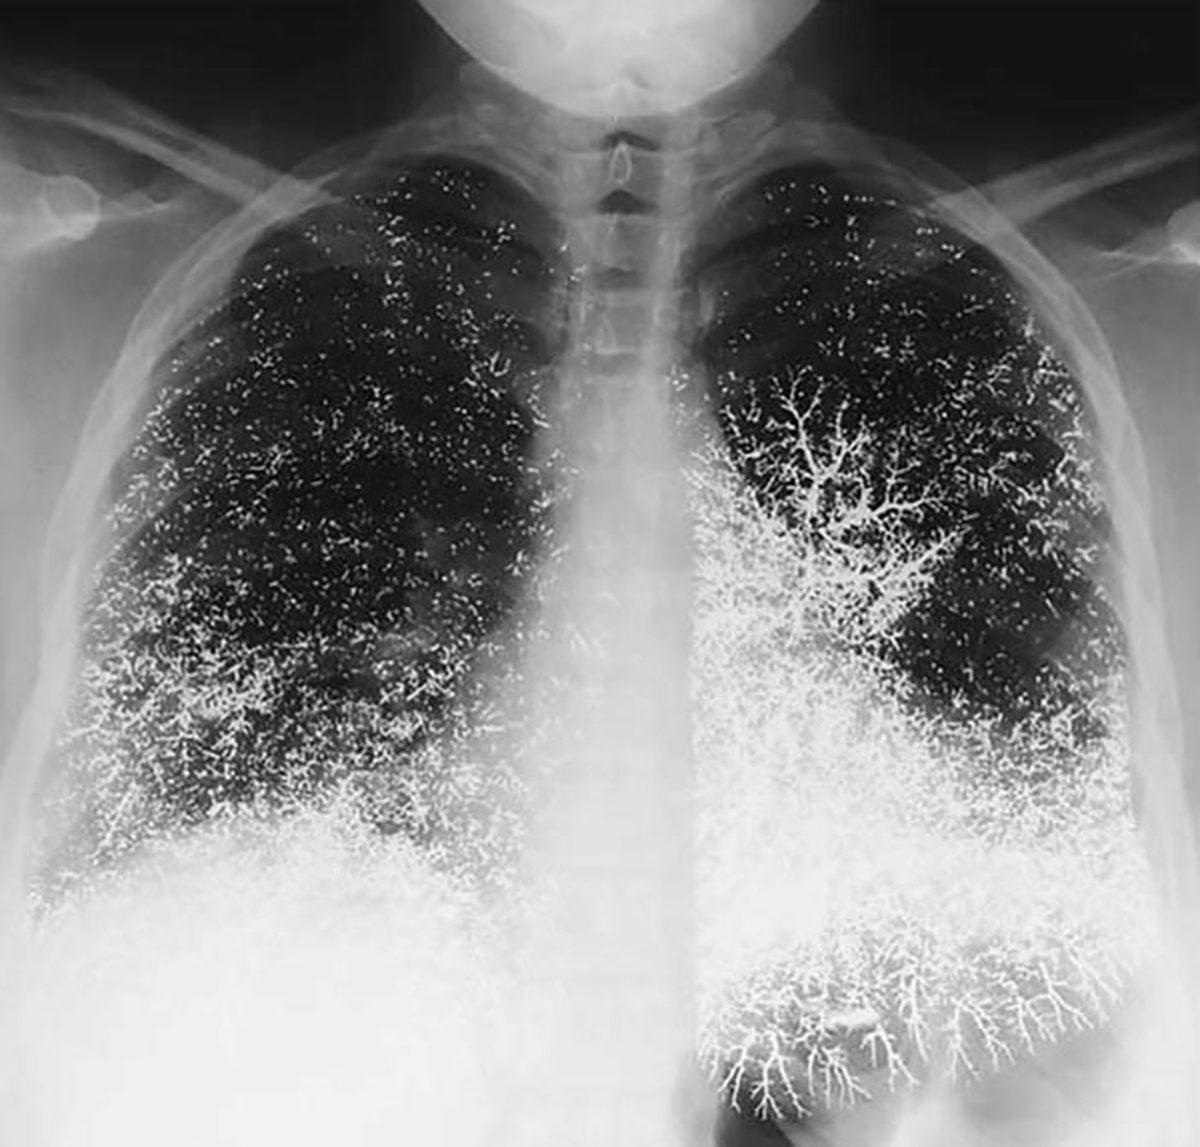

- Damar yoluyla kendisine elemental enjekte ederek intihar girişiminde bulunan birinin göğüs röntgeni.